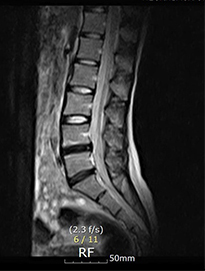

디스크내장증을 다른 말로 블랙디스크(black disc)라고 부르기도 하는데, MRI 검사 영상을 보면 디스크 부분이 검게 보이기 때문에 블랙디스크라고 부릅니다. 디스크 내의 수분이 빠지면서 탄성이 떨어지고 퇴행이 진행되어 검게 보이는 것인데요. 이처럼 아직 디스크가 탈출하지 않아 방사통이나 저림 증상이 없다고 하더라도 이미 퇴행이 진행된 상태라 이는 퇴행성 디스크의 일종이라 볼 수 있습니다. 하지만 중요한 것은 까맣게 변성된 디스크가 직접 통증을 일으키는 원인이 아니고 허리 근육 기능이 약화되고 심각한 기능적인 문제가 통증의 직접적인 원인입니다.

디스크내장증은 디스크가 탈출된 것이 아닌

디스크만 퇴행된 것이므로, MRI영상으로 보면

신경이 지나가는길이 깨끗하다는 것

이 특징입니다.